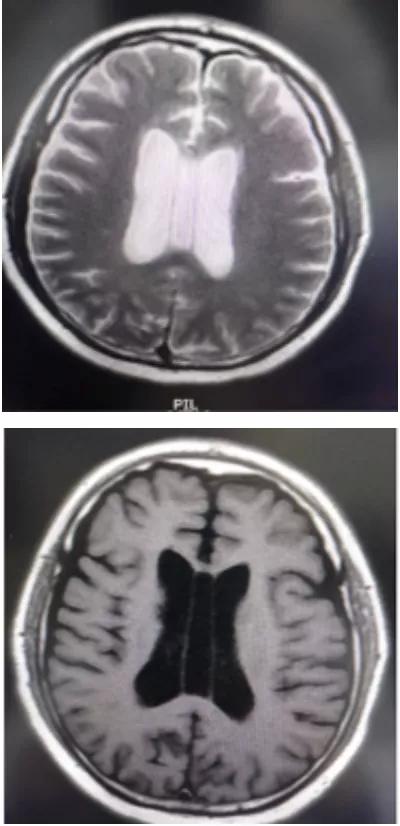

透明隔腔(CSP) 的前上方为胼胝体,后下方为穹隆。侧壁即透明隔小叶。透明隔腔≤3mm,描述可见透明隔腔。

1.胼胝体膝部;2.透明隔腔;3.穹隆柱;4.穹隆体;5.穹隆脚;6. Vergae腔;7.胼胝体压部

透明隔腔增宽是透明隔腔≥3mm,直径<10mm,描述可见透明隔腔增宽,透明隔的两壁呈前后平行排列,边界清晰,或内凹,对周围组织无压迫,为正常生理变异,临床无症状。透明隔腔≥10mm,描述可见透明隔腔明显增宽。

MR检查为诊断第五脑室的主要手段。第五脑室在MRI上通常表现为脊髓圆锥内边缘清楚的卵圆形囊腔,形态规则,囊壁光整,且与周围正常的脊髓组织分界清楚,囊内为T1WI低、T2WI高的脑脊液信号,囊内分隔及囊周水肿性改变比较少见,增强扫描后囊壁不强化。第五脑室需要与位于脊髓圆锥的囊性肿瘤如室管膜瘤、星形细胞瘤以及脓肿相鉴别,囊性肿瘤和脓肿的囊壁通常有不同程度的强化。脊髓圆锥的转移瘤很少见,MRI表现通常为肿瘤强化且周围伴有明显水肿。脊髓背侧的严重损伤也可发展为囊性病灶,但目前报道的大多数第五脑室病例并无外伤病史。脊髓内的表皮样囊肿和皮样囊肿由于成分复杂导致MRI表现多变,而第五脑室的MRI表现单一。